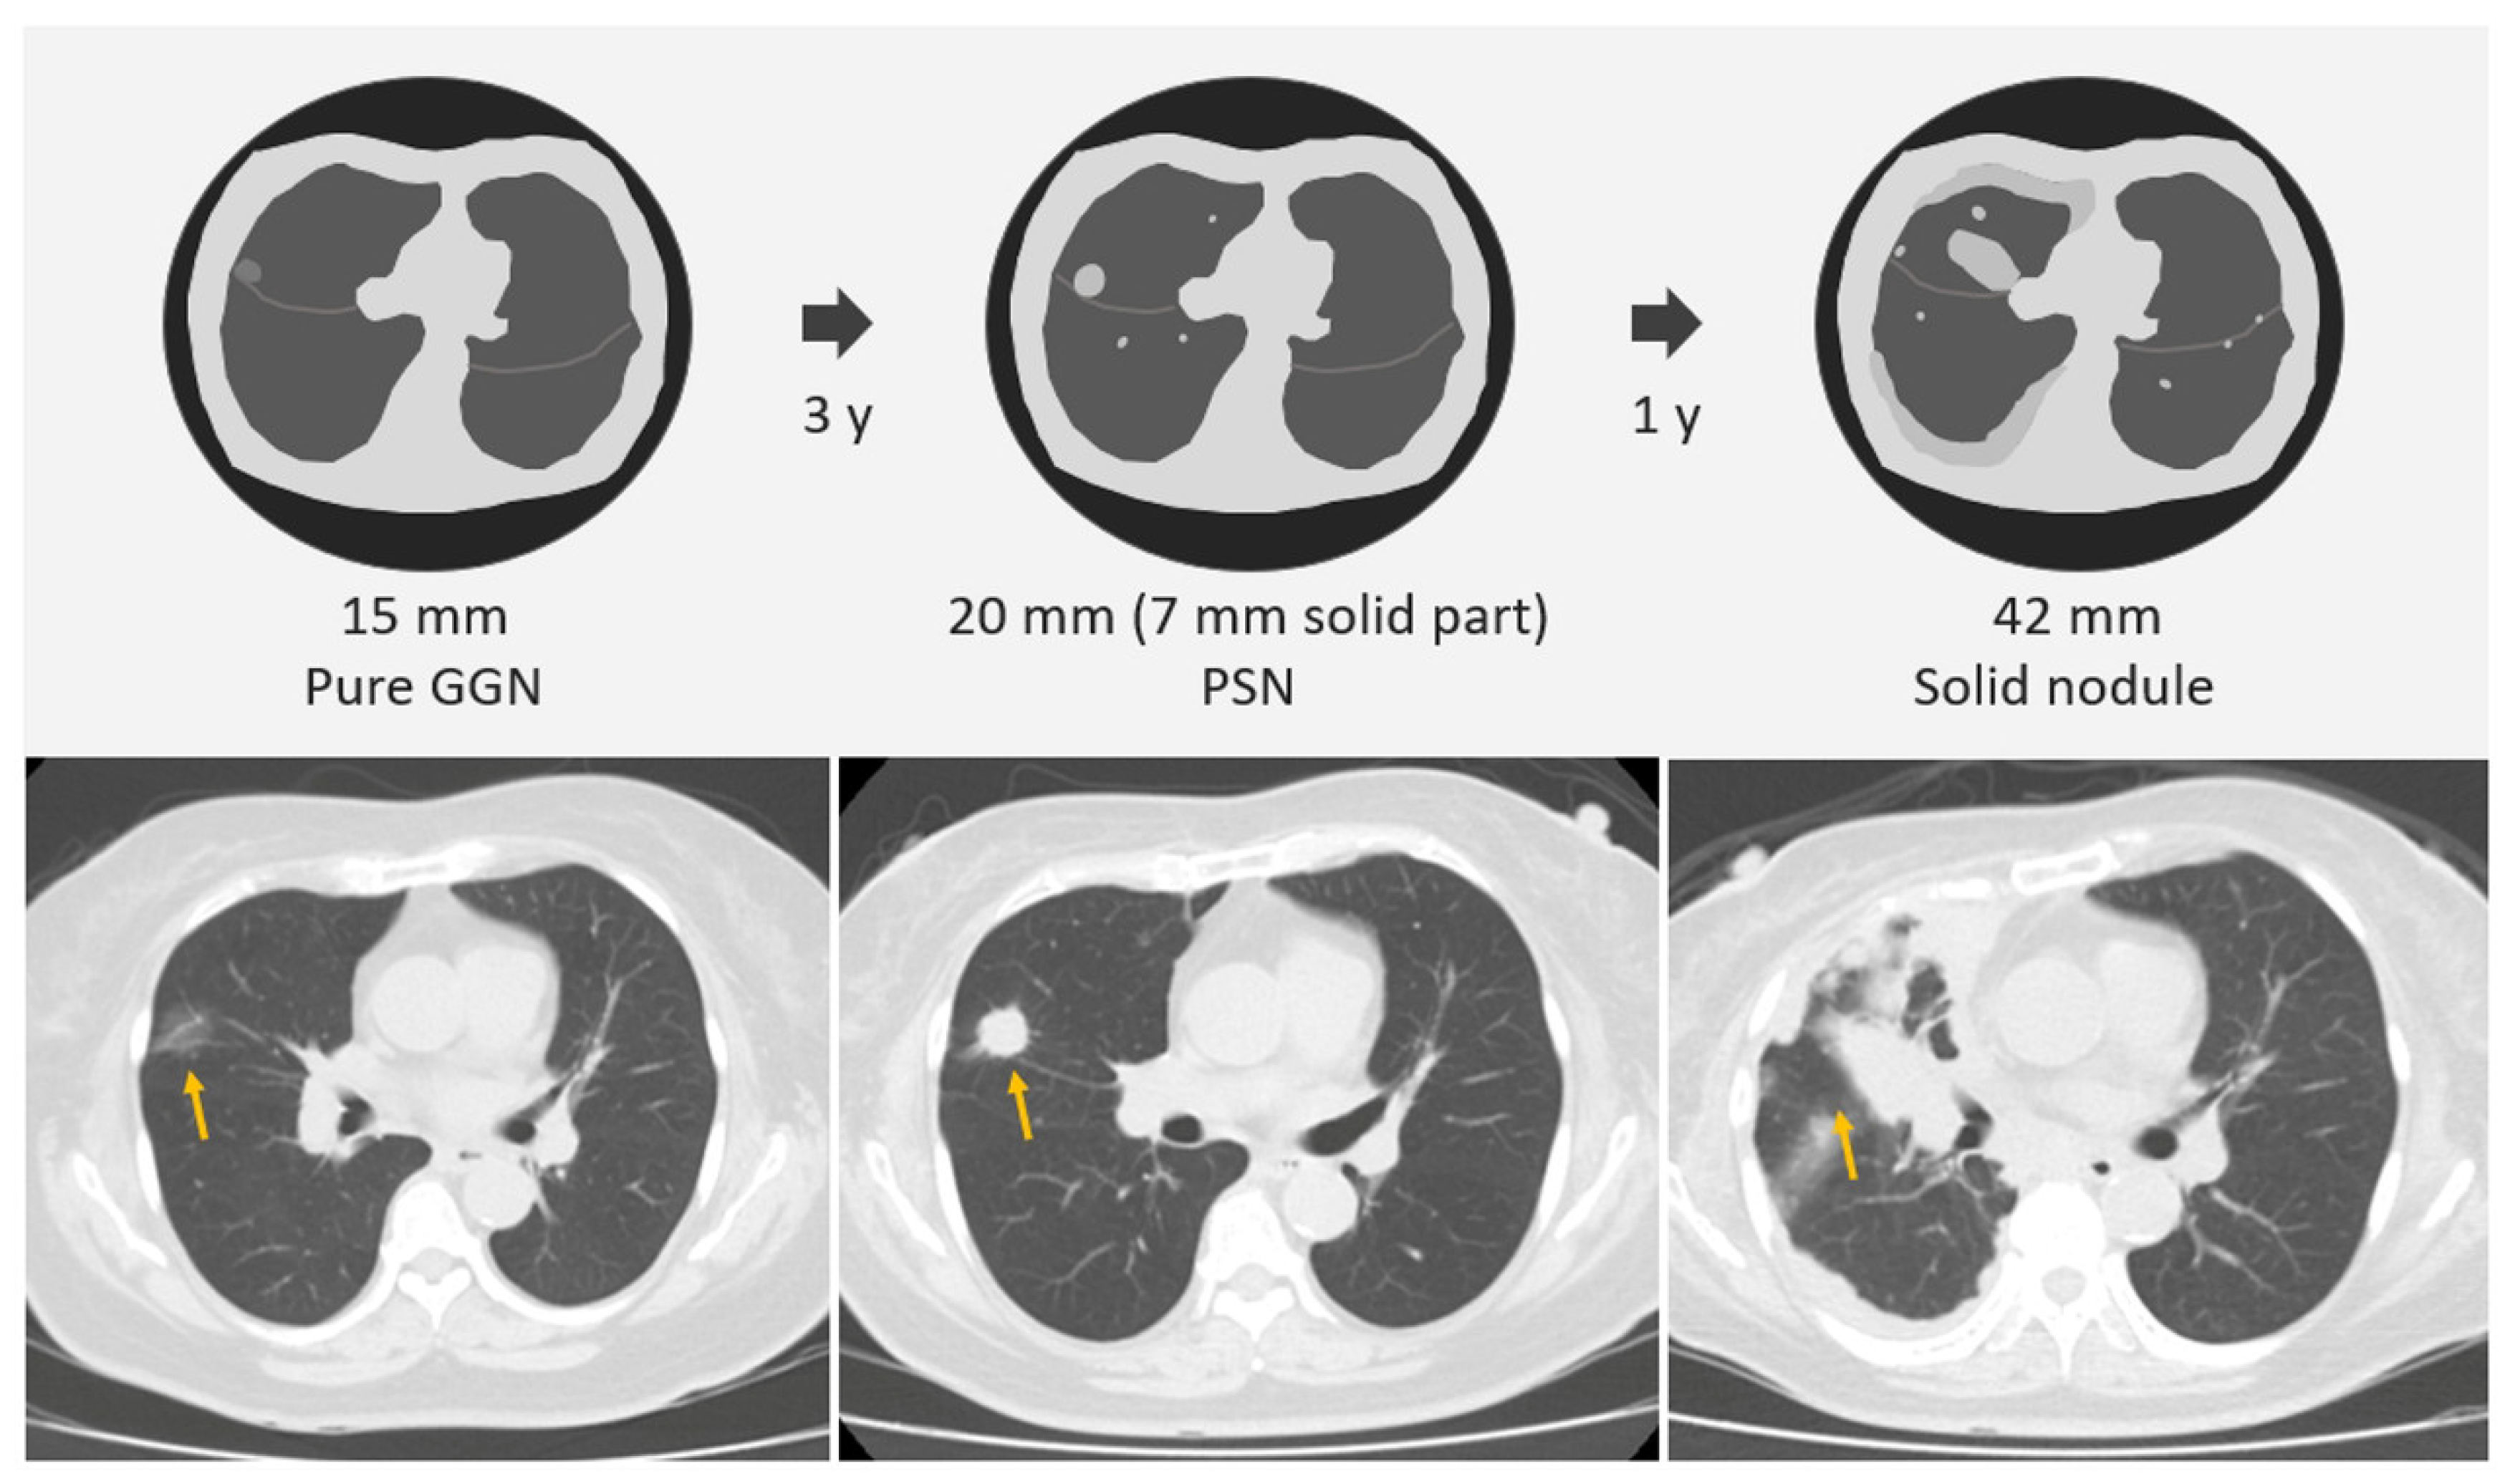

2.1. SSNs Interval Growth with an Increase of ≥2 mm

2.3. SSNs Interval Growth with Clinical Stage Shift